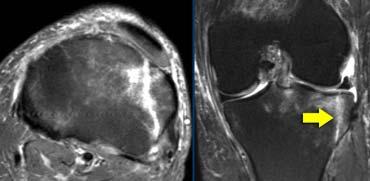

Trật khớp xương bánh chè

Giải phẫu bình thường

Sụn xương bánh chè là sụn dày nhất trong cơ thể. Bề mặt sụn cần có đường viền nhẵn đều.

Thành phần quan trọng nhất của mạc giữ phía trong là dây chằng xương bánh chè – lồi cầu đùi phía trong, bám tận ra phía sau ngay trước dây chằng bên trong (MCL).

TRÁI: Dập xương lồi cầu ngoài (vòng tròn vàng). MCL bình thường (mũi tên xanh lá) nhưng không thấy dây chằng xương bánh chè – lồi cầu đùi phía trước. PHẢI: Dây chằng xương bánh chè – lồi cầu đùi phía trong bị đứt khỏi điểm bám tại xương đùi.

Ca bệnh bên trái là một nữ cầu thủ bóng đá bị xoắn vặn khớp gối.

Bốn hình ảnh MRI từ dưới lên trên thể hiện đầy đủ các đặc điểm hình ảnh của trật khớp xương bánh chè kèm đứt dây chằng xương bánh chè – lồi cầu đùi phía trong.

Xương bánh chè bị trật và mặt khớp phía trong đã va đập vào lồi cầu ngoài xương đùi.

Xương bánh chè đã tự trở về vị trí bình thường.

Tổn thương dập xương có thể kèm theo biến chứng gãy sụn khớp.

Trật khớp xương bánh chè (2)

Trật khớp xương bánh chè là một tình trạng thường gặp, nhưng thường bị bỏ sót trên lâm sàng do xương bánh chè tự trở về vị trí bình thường sau khi trật.

Bệnh nhân đến khám với hình ảnh gối sưng đau, có thể gợi ý nhiều chẩn đoán khác nhau từ đứt dây chằng chéo trước (ACL), dây chằng bên trong (MCL), rách sụn chêm cho đến gãy xương.

Do đó, các đặc điểm hình ảnh trên MRI đóng vai trò quan trọng trong việc nhận diện tình trạng này.

Những bệnh nhân có dị vật khớp hoặc trật khớp tái diễn có thể được chỉ định phẫu thuật tái tạo mạc giữ.